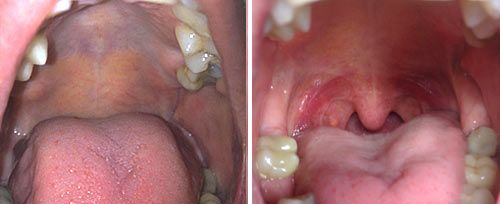

Liệu pháp NightLase® của Fotona là điều trị laser thân thiện với bệnh nhân nhằm tăng cường chất lượng giấc ngủ của người được điều trị. NightLase® có thể giảm bớt hậu quả và biên độ ngáy bằng một điều trị laser nhẹ nhàng tác dụng lên mô niêm mạc.

Phương thức phát xung laser độc quyền của Fotona tối ưu hóa độ dài các xung, giúp làm nóng mô niêm mạc miệng một cách an toàn. Cách làm này đủ nhẹ nhàng để sử dụng trên các mô nhạy cảm trong miệng, nhưng cũng đủ mạnh để tạo hiệu quả làm nóng về mặt lâm sàng.